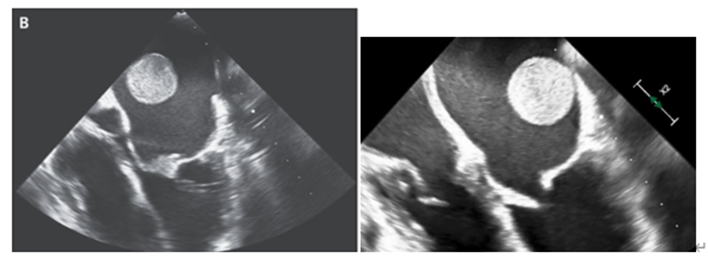

UCGでは重度の両心機能不全、severe MS、左房内には2.7㎝の可動性の血栓を認めた。

(エコー状球体の塊が左房内を移動している様子が見て取れる)